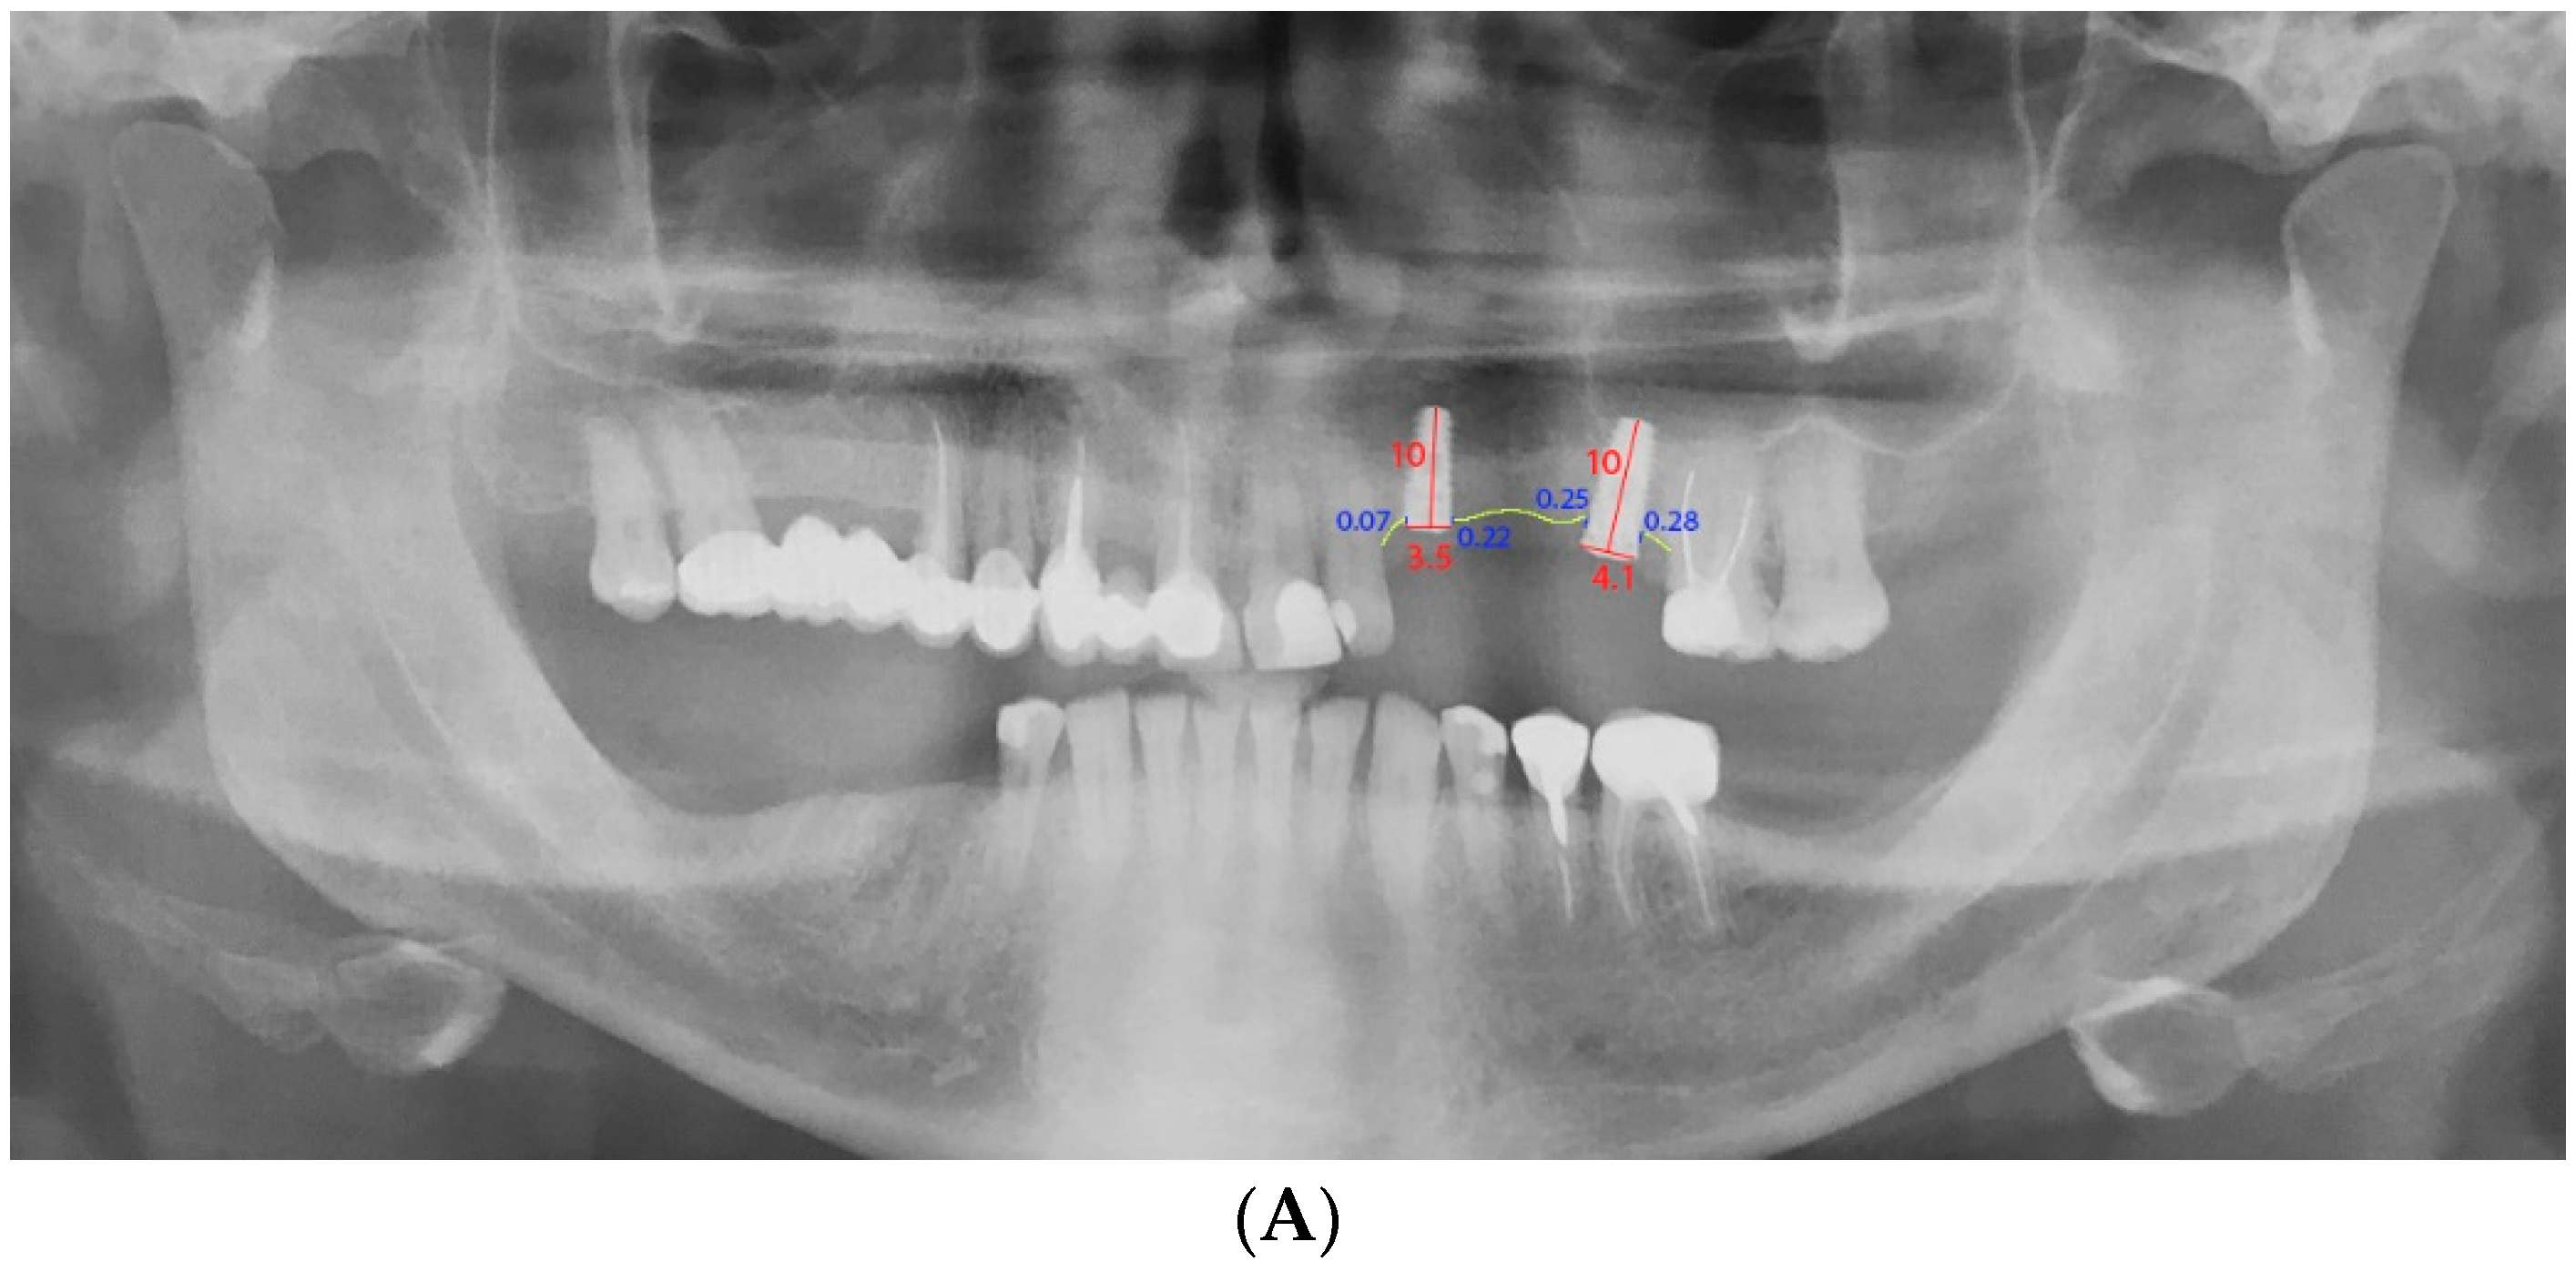

2.7. Radiographic Monitoring of Bone Loss

3.4. Bone Loss